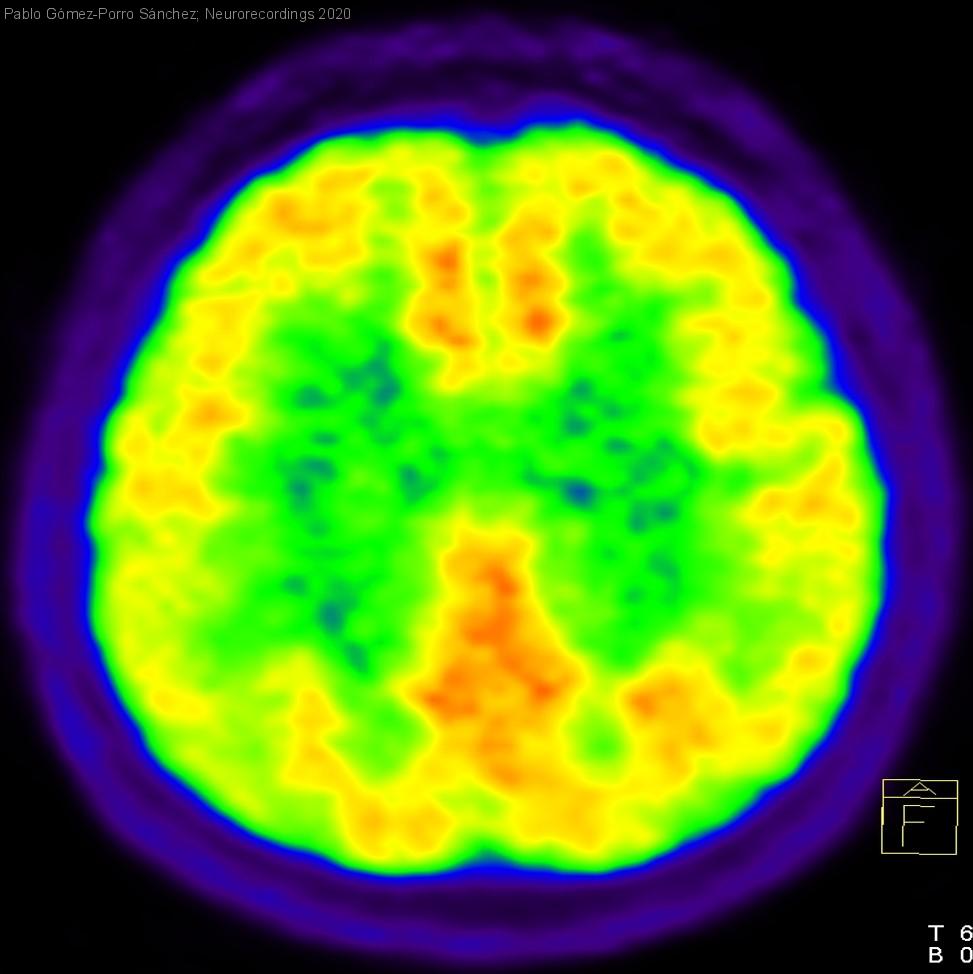

Hombre | 53 años

Diagnóstico final: Enfermedad de Marchiafava-Bignami

Varón de 53 años, con enolismo grave que acude por disartria, inestabilidad y alteraciones cognitivo-conductuales de dos semanas. Se evidencia somnolencia, bradipsiquia, apatía, abulia, desorientación temporal, hipoprosexia, afectación de la memoria episódica, disartria, ataxia truncal que...